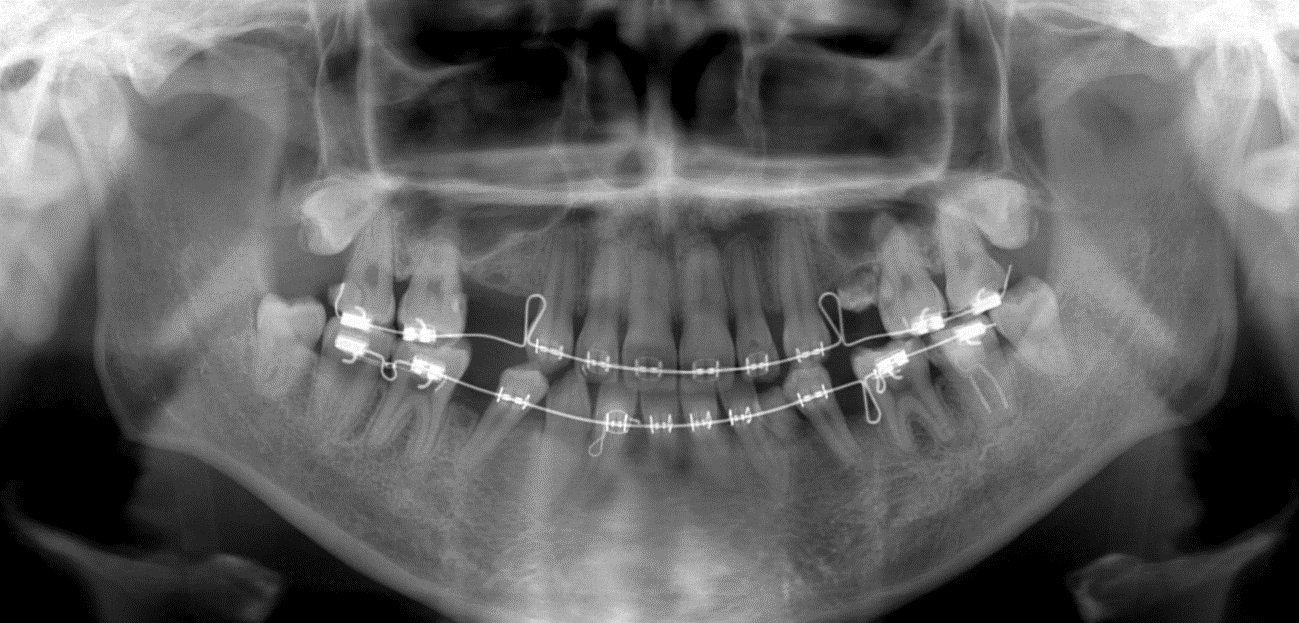

写真1 には、大人になってから、最終的に補綴歯科治療を行うことを前提として矯正歯科治療を行っている例で、上あご左右の第1と第2小臼歯(4番目と5番目の永久歯)と、下あご右側の第2小臼歯、左側の犬歯(3番目の永久歯)と第2小臼歯7本が欠如した症例をご紹介します。歯を補うために適切に空隙を開けるようにしたり、歯の傾きを変えたりしています。

写真1